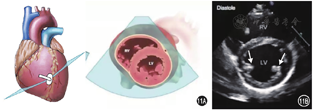

在左心室短轴二尖瓣水平切面基础上探头进一步向心尖部倾斜,也可在探头保持显示左心室短轴二尖瓣水平切面的方位和声束方向,位置向左下移动(图11,视频9)。

注:RV右心室;LV左心室

右心室前壁、右心腔、左心室腔,乳头肌、左心室前壁、间隔(前间隔、下壁间隔)、下壁、侧壁(下侧壁、前侧壁)和心包膜。

(1)观察室间隔和左心室壁的位置、厚度、整体结构、节段性运动状况,观察左心室腔形状、内径、腔内结构和功能;尤其对冠心病的评价具有重要意义。

(2)观察乳头肌的位置、结构和活动状况等。